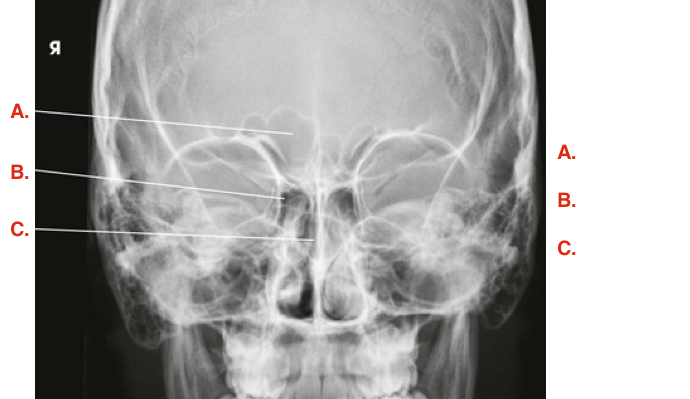

Question

Label the image

Image:

28ae48a7-dc88-4618-9bf9-49d13f361e8d (image/png)

Answer

frontal sinuses

ethmoid sinuses

sphenoid sinuses